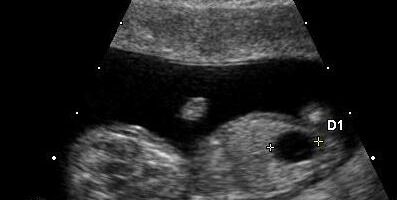

Echogenic Kidneys in the Fetus: What Parents Need to Know